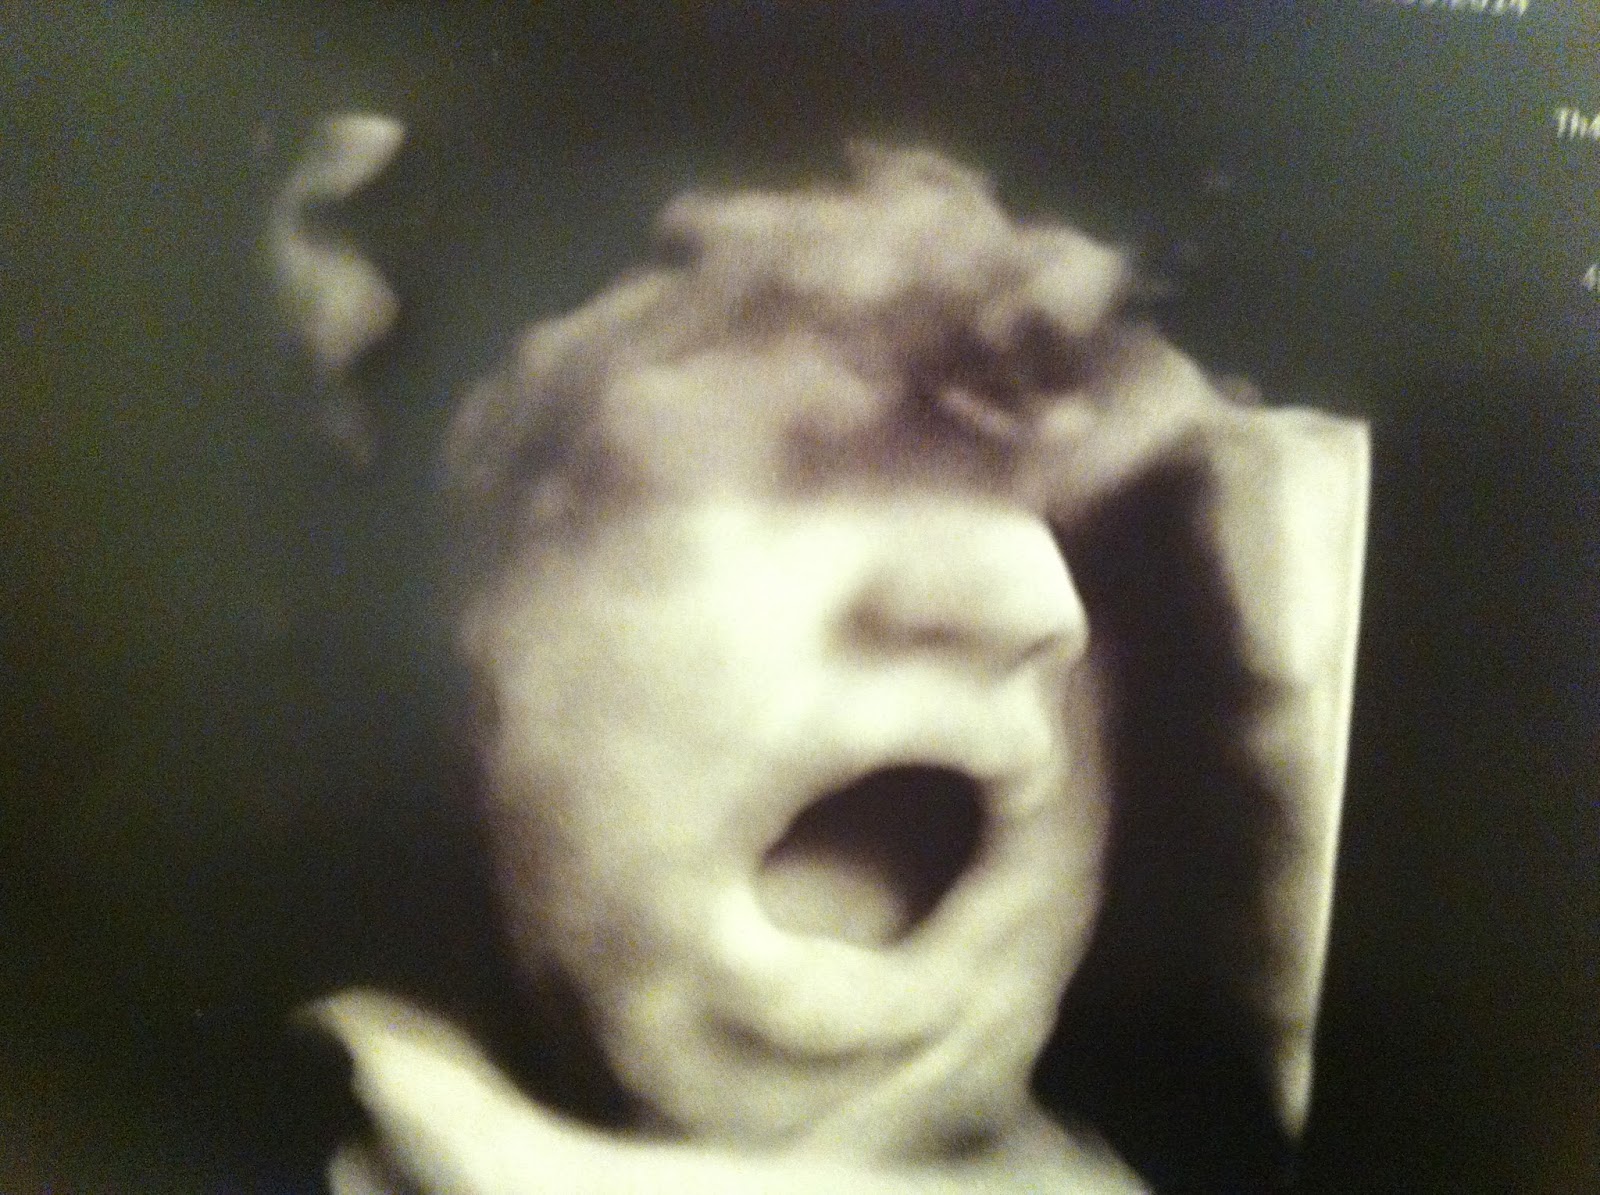

Baby M pesa neste momento 2 quilos, está bem bochechudo, e pelos vistos grama abrir a boca (já na ecografia anterior foi apanhado nesta linda figura). Não sei se está sempre a ver se petisca alguma coisa (quem sai aos seus não degenera), ou se está a treinar para ser um berrador profissional. Entre uma e outra, estou a apostar as fichas todas na primeira. Prefiro uma lontrinha a uma sirene dos bombeiros.

Por outro lado, e olhando bem… baby M parece ter a mão na testa, em jeito de preocupação.

Se calhar ficou tão horrorizado como eu com a visita de hoje a uma contabilista e está a reeditar "o Grito", de Munch. É bem capaz de ser isso.